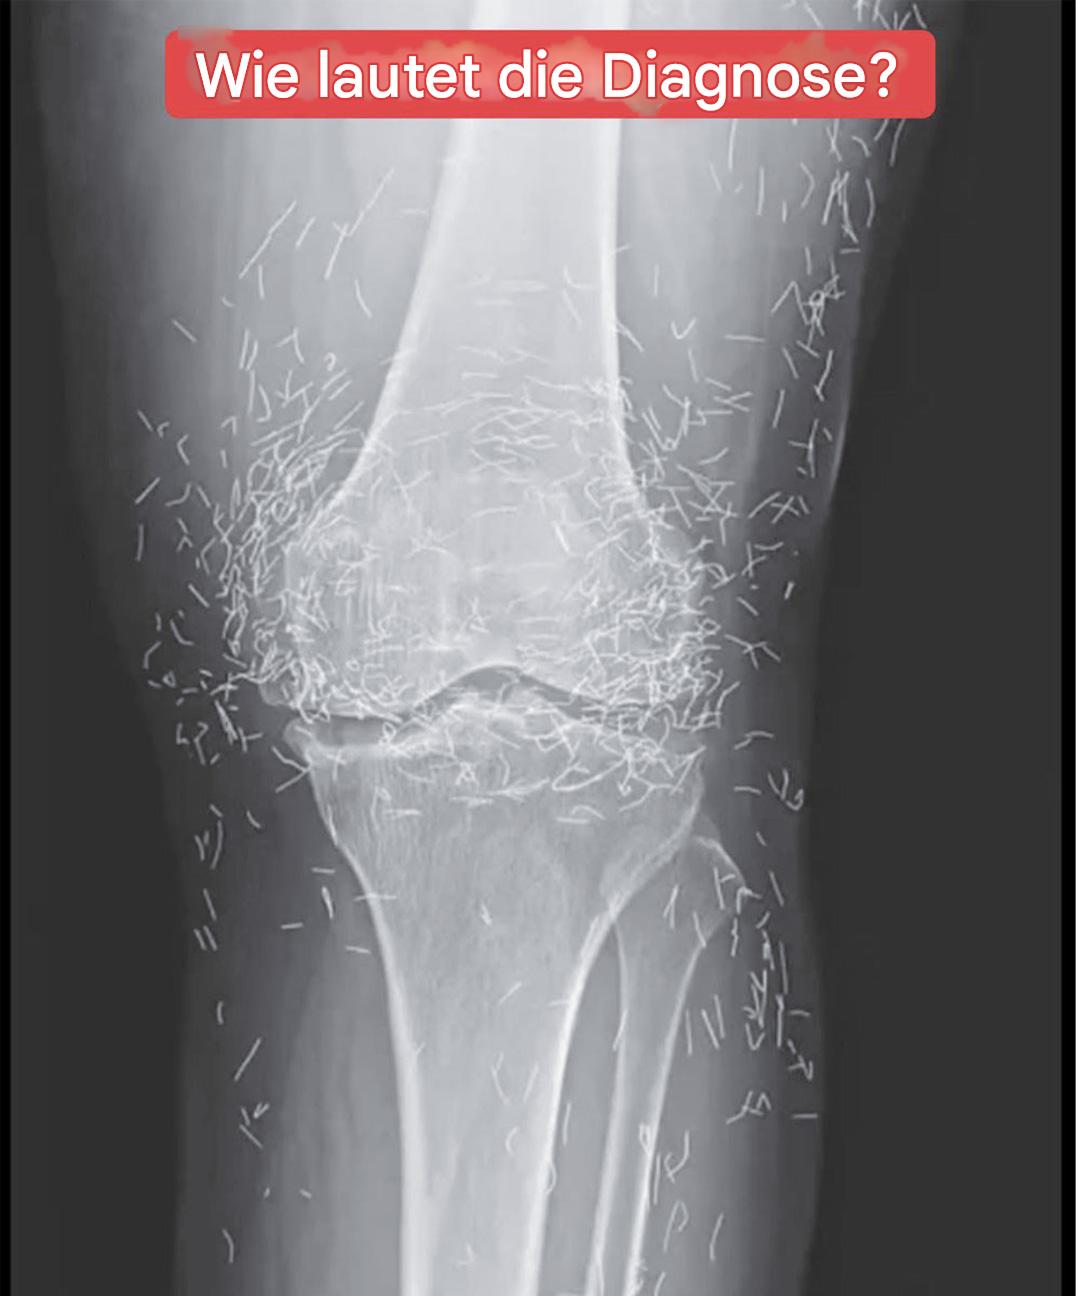

Bei einer routinemäßigen Röntgenuntersuchung entdeckten die Ärzte zu ihrer Überraschung Hunderte kleiner, glänzender Nadeln, die um seine Knie verstreut waren. Eine wahre medizinische Kuriosität, die sowohl Erstaunen als auch Vorsicht weckte. Denn obwohl Gold ein inertes und gut verträgliches Metall ist, ist die längere Anwesenheit von Fremdkörpern im Körper nie ungefährlich.

Laut Experten für medizinische Bildgebung können diese Nadeln bestimmte Körperbereiche auf Röntgenbildern verdecken und so die Diagnose anderer Probleme erschweren. Vor allem erschweren sie die MRT-Untersuchung erheblich: Es besteht die reale Gefahr, dass sich die Nadeln unter dem Einfluss des Magnetfelds bewegen und empfindliches Gewebe schädigen.